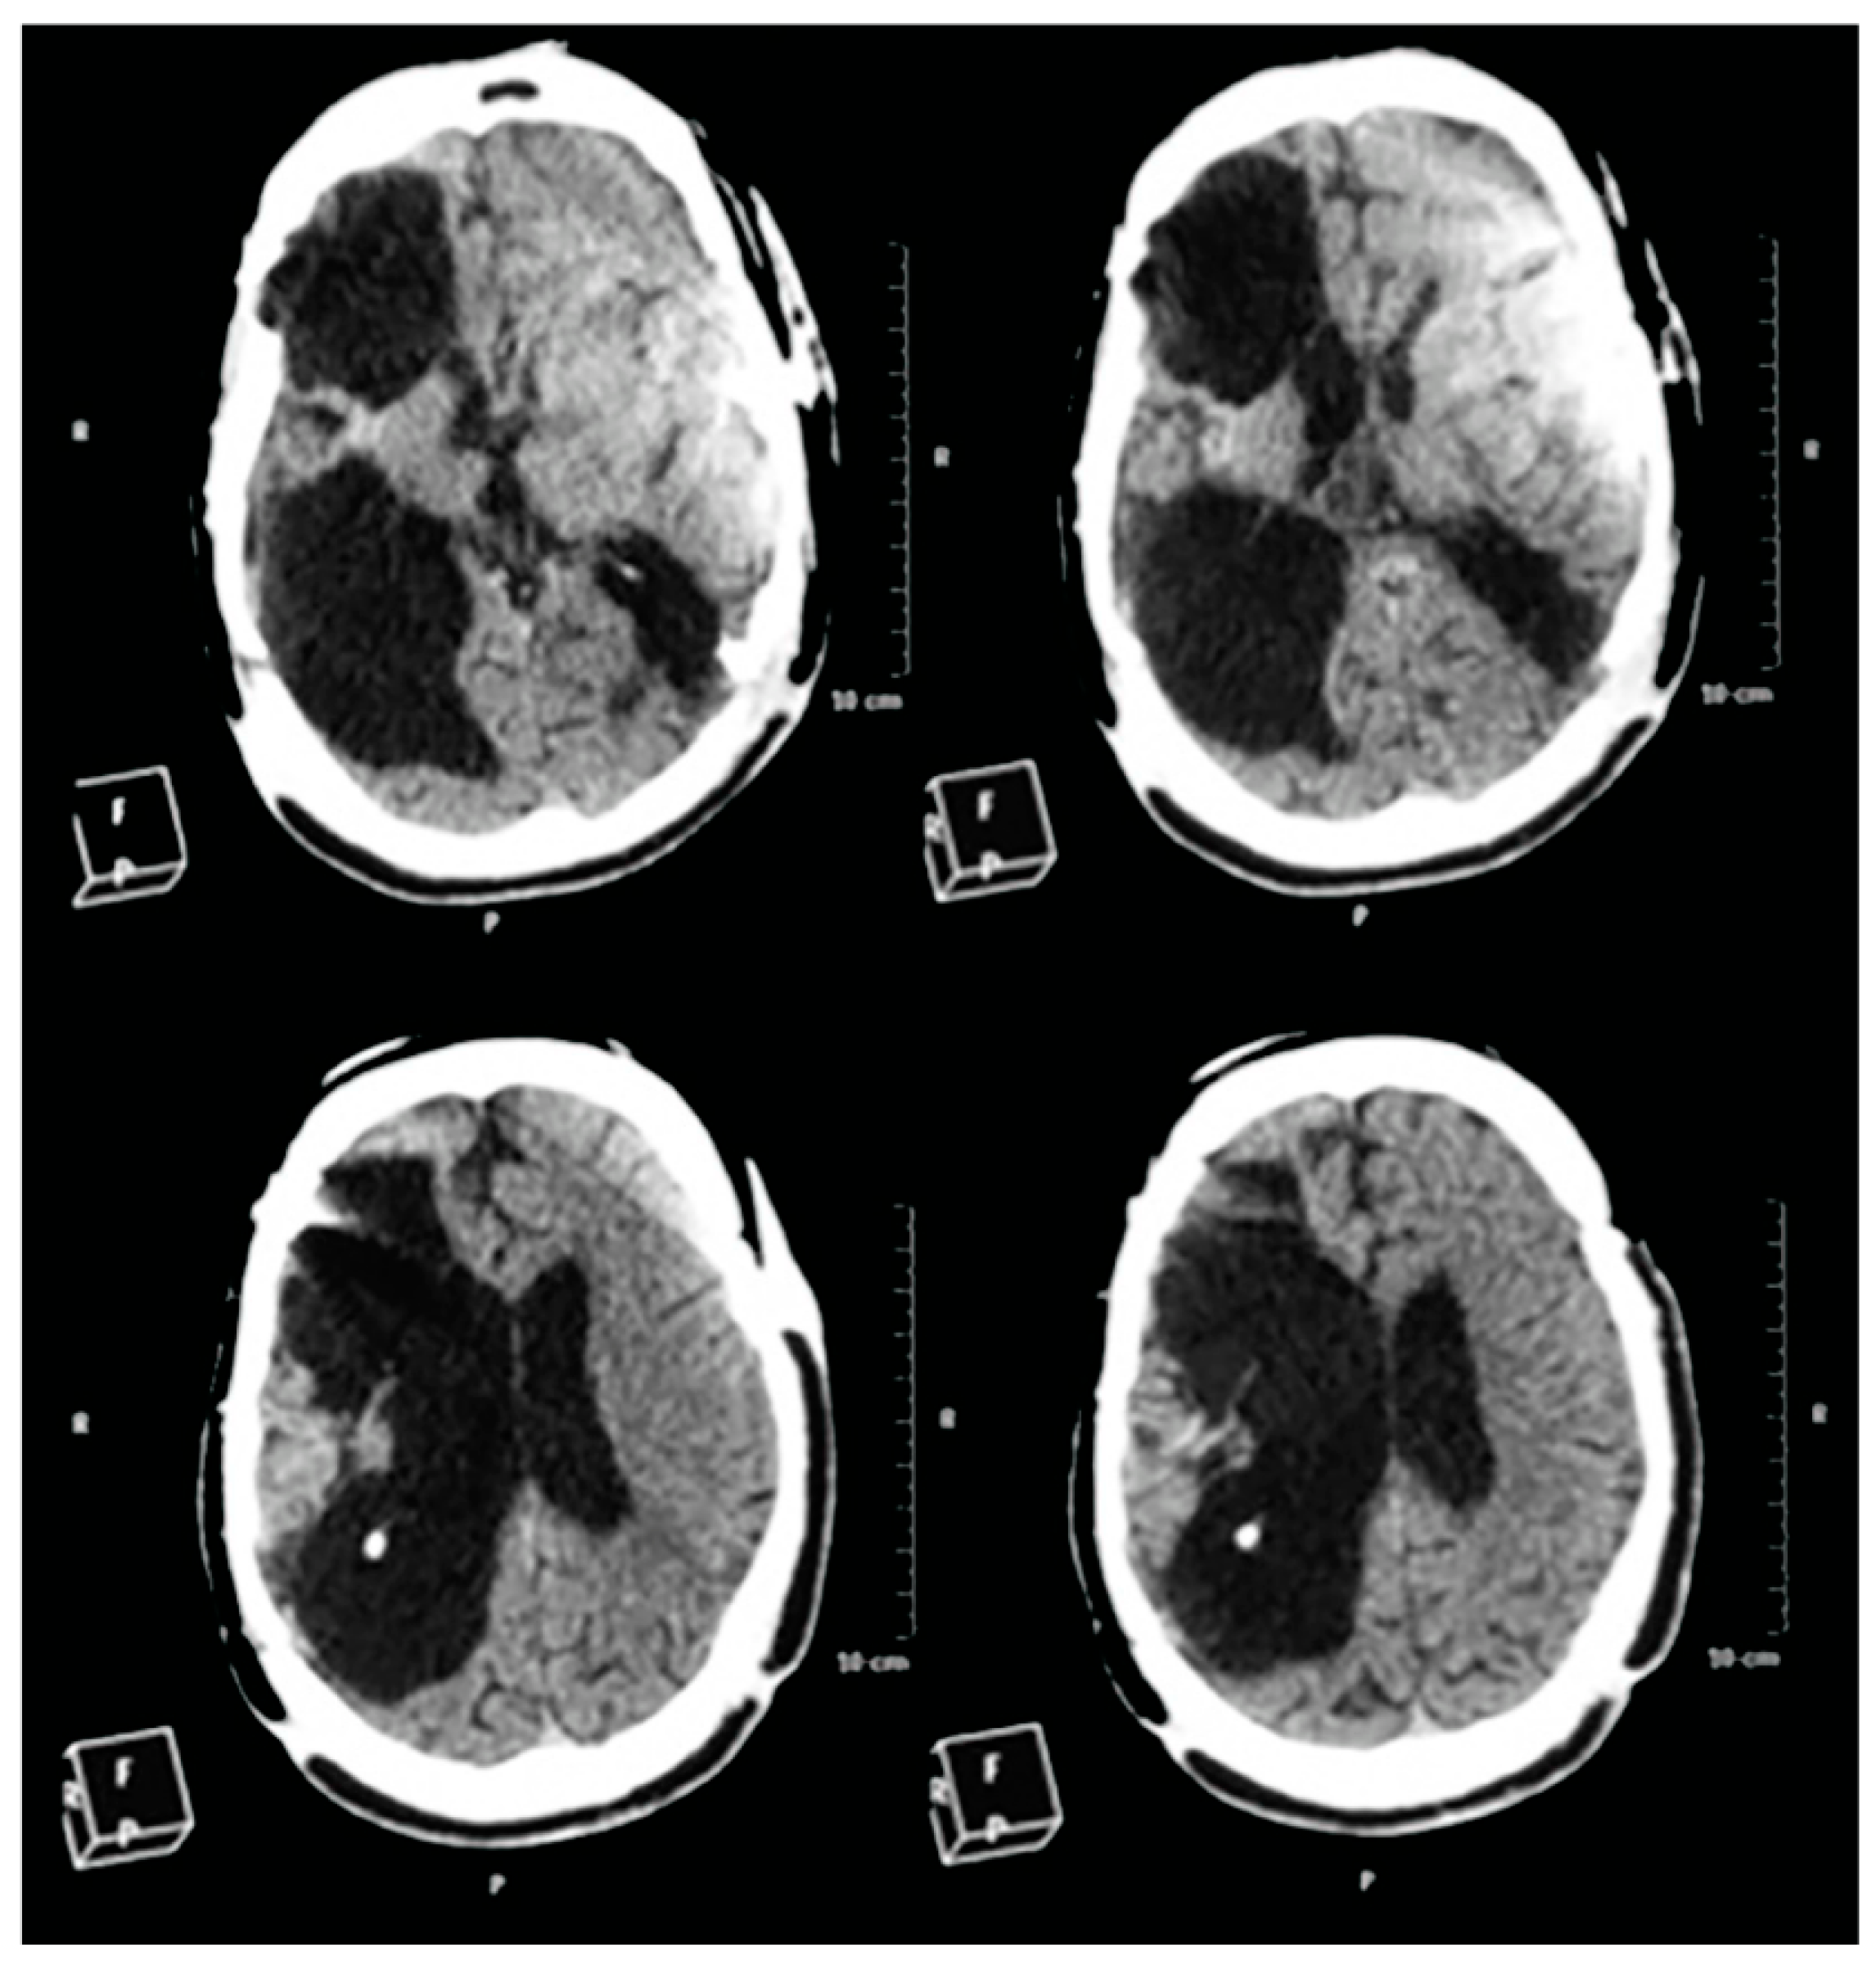

2.5. CT-Scan